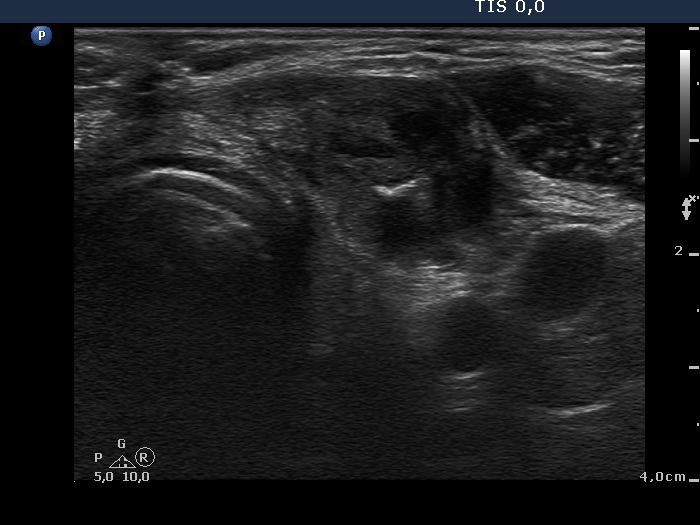

Eleven years after surgery (second and third rows of images):

Clinical data: The patient came to a follow-up. He told us that he decided not to visit the surgeon because the mass did not cause any complaints. He didn't remember exactly, but a few years ago he couldn't feel the knot at all, it had slowly disappeared on its own over the years.

Palpation: no abnormality.

Laboratory tests: TSH 3.56 mIU/L on daily 75 microgram levothyroxine.

Ultrasonography. The right lobe remained unchanged. Compared with the previous finding, a much smaller, inhomogeneous mass was found according to the left lobe. A few centimeters above and ventral to the left lobe, a cystic lesion was found within the strap muscle and close to this, an amorphous hyperechoic fragment was also present (see video).